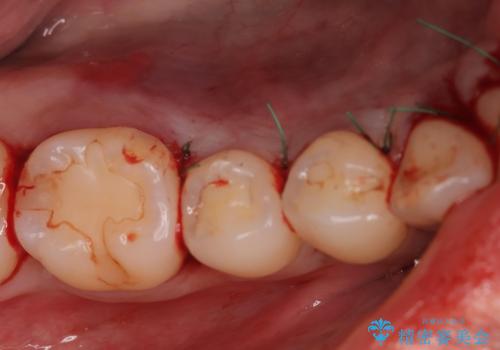

- 下顎の骨隆起を取りたいとのことで来院された患者様です。

右側と左側で2回に分けて行いました。

術後1週間での抜糸となります。